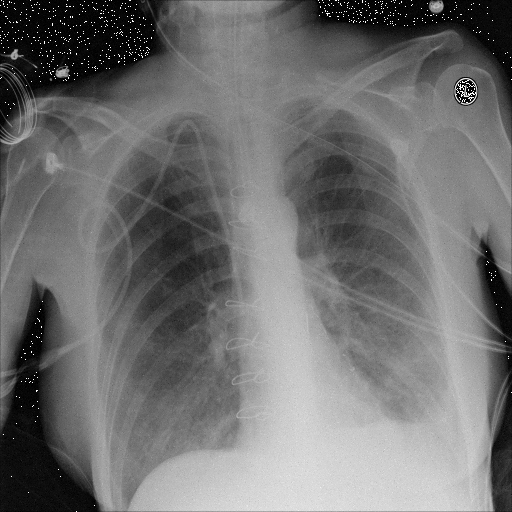

Refer to caption

(a) Original,

case 5 (simulated situs inversus).

(b) ϵ=102HWitalic-ϵsuperscript102𝐻𝑊\epsilon=10^{2}\cdot H\cdot W,

case 5.

Figure 5: Flip obfuscation with the image domain LDP.

Figure 6: Flip obfuscation with DP-GLOW.

Here, we assume two possible privacy leakage scenarios. To CXR images, we intentionally add features that can lead to the re-identification of the subject appearing in a CXR image. The first feature is an artificial block marker. The second feature is a rare anatomical abnormality known as situs inversus simulated by flipping a CXR image along the vertical axis. Figs. 3(a) and 3(c) show CXR images with the artificial block marker. Fig. 5(a) shows a flipped CXR image to represent a case of situs inversus. We applied DP-GLOW to these CXR images. In Figs. 3(b) and 3(d), the image domain LDP fails to obfuscate the artificial block marker with a moderate privacy budget. In contrast, in Figs. 4(b) and 4(d), DP-GLOW successfully obfuscated the artificial block marker with the moderate privacy budget. On the other hand, the anatomical shape of the chest and the abnormal opacity (hilar regions in the case 1) are preserved. In Fig. 5(b), we observed that the right edge of the heart does not become obfuscated with the image domain LDP. In contrast, in Fig. 6(b), we observed that the right edge of the heart becomes obfuscated and the heart appears at the center of the thoracic cage with DP-GLOW. However, DP-GLOW with this privacy budget is insufficient to almost completely erase the feature of situs inversus.